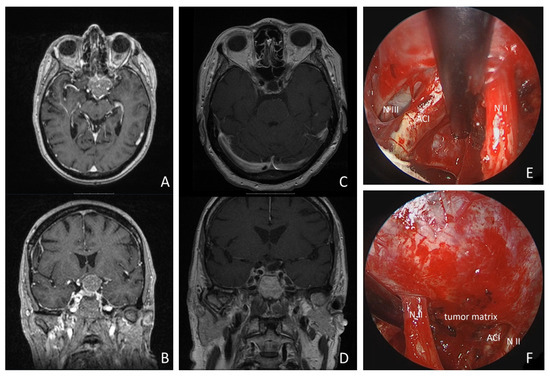

Meningiomas of the Skull Base: order now in the Thieme Webshop。Endoscopic-Assisted Microsurgical Meningioma Resection in the。fonc-10-01054-g001.jpg。Surgery of Skull Base MeningiomasM.Samii 著こちらは裁断済みの商品です。Skull base invasive low-grade meningiomas, a distinct genetic。新品の本を業者に頼み裁断したので、とても良い状態だと思います。標準 整形外科学15版。定価:17672円(amazon)#脳神経外科 #脳外科 #血管内治療 #神経内科 #耳鼻咽喉科 #耳鼻科 #手術 #専門医 #脳卒中 #脳腫瘍 #頭蓋底

• Endoscopic-Assisted Microsurgical Meningioma Resection in the

• fonc-10-01054-g001.jpg